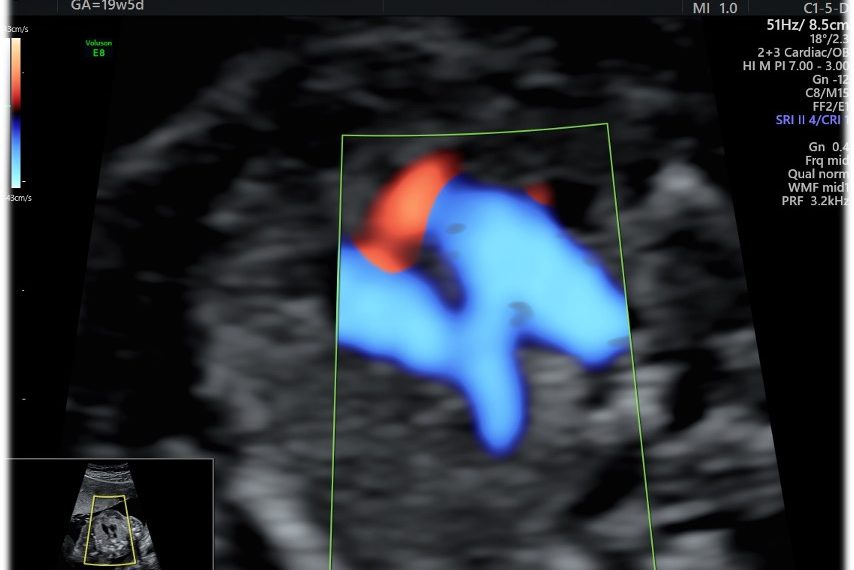

Risposta Caso del mese SIEOG ottobre 2024

Risposta caso sieog ottobre 2024